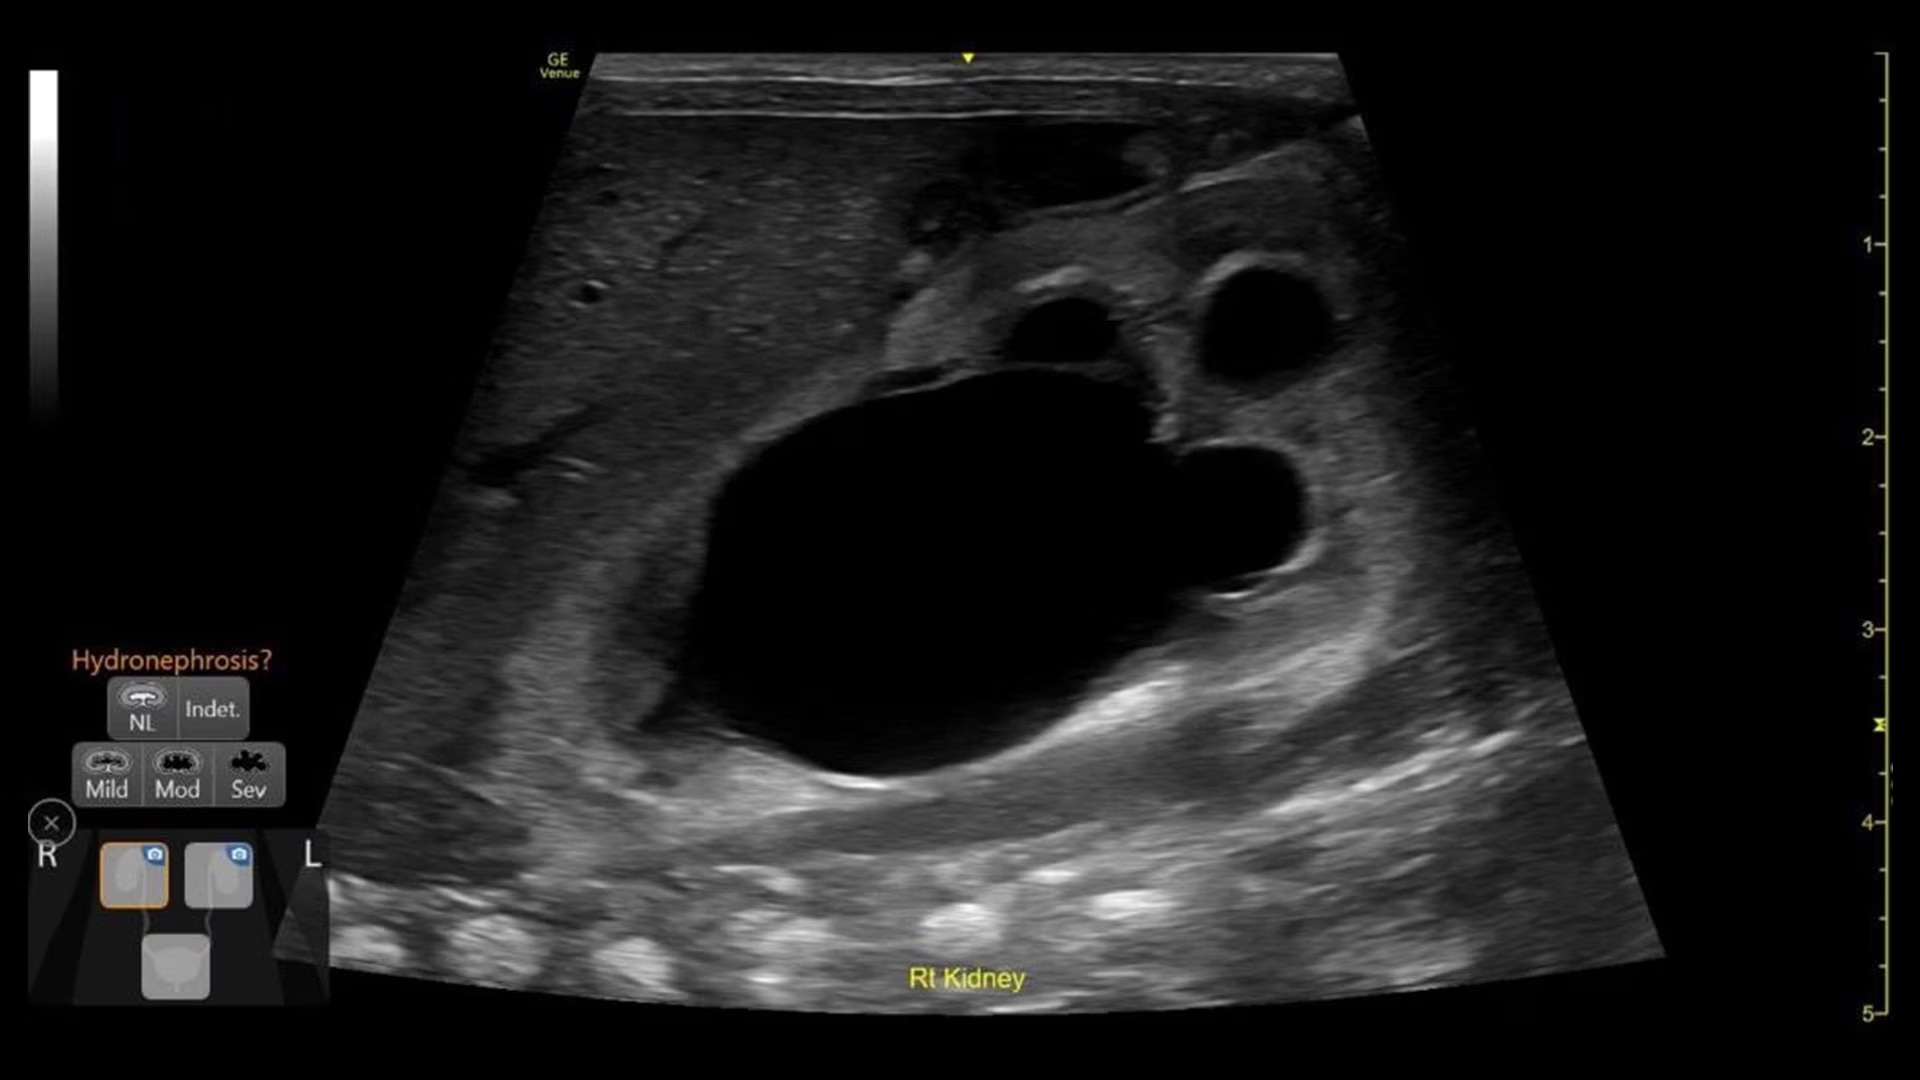

Quickly assess kidneys and the bladder with Renal Diagram

Simplify documentation and provide easy follow up for patients with suspected hydronephrosis. No need to type findings; simply assign a label from a pre-populated list that correlates with images.